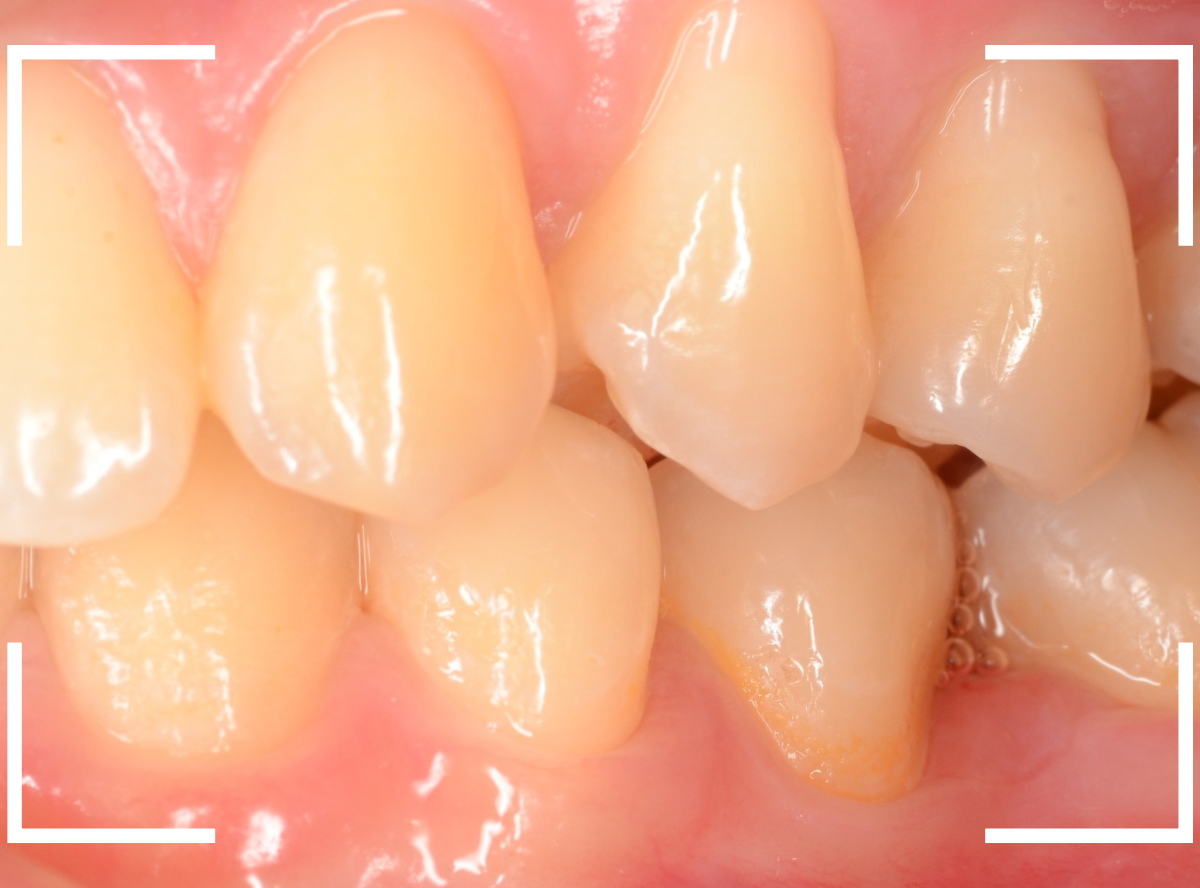

Case.29

舌のそばの虫歯とセラミック治療

下の奥歯が虫歯になった患者さんのケースです。

〇部が虫歯の部分です。

写真で見てわかるように、常に舌が歯に触っているような状況です。

このような場合、虫歯を見つけづらいですし、治療の難易度もあがります。